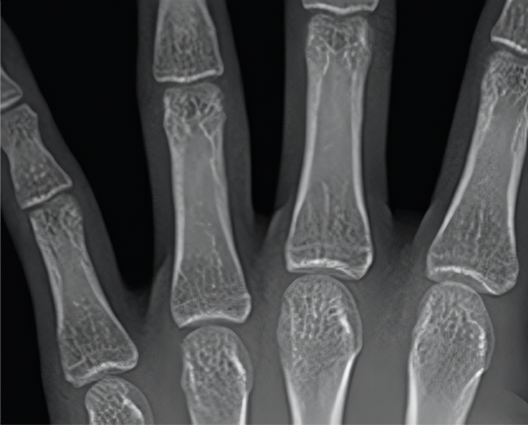

교정치료의 골든타임, 소아 교정 성장 예측 케어

우리 아이 뼈의 성숙도를 판단하고

이를 토대로 성장 정도를 평가하여

성장 교정 시 참고 자료로 사용합니다.  뼈의 성숙도를 통해서

더 정확한 교정 시기 예측

이 가능할 수 있습니다.

• 열린 성장판

• 닫힌 성장판